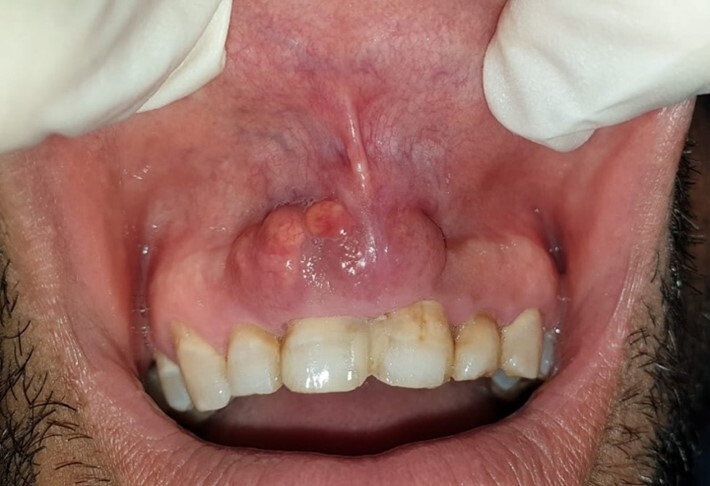

罗赛-多夫曼病(RDD)由 J Rosai 和 R F Dorfman 于 1969 年首次描述,是一种病因不明的良性、自限性组织细胞增生症。它通常出现在生命的头二十年。最常见的临床表现是无痛性双侧颈淋巴结病,伴有发热、体重减轻和血沉增快。然而,无结节受累的 RDD 极其罕见,最常见的结节外部位是头颈部,主要累及鼻腔、咽部和副鼻窦。口腔部位的罗赛-多夫曼病偶见;据我们所知,文献中仅发现 17 例无淋巴结受累的口腔罗赛-多夫曼病。由于这些孤立的口腔表现非常罕见,因此需要对其临床和放射学方面进行更多的研究。本文旨在介绍一例罕见的无淋巴结受累的口腔罗赛-多夫曼病病例,详细介绍其临床和影像学表现,以及对我们的患者所采用的治疗策略。

First described by J Rosai and R F Dorfman in 1969, Rosai-Dorfman disease (RDD) is a benign, self-limiting histiocytosis of unknown etiology. It is usually seen in the first two decades of life. The most frequent clinical presentation is painless, bilateral cervical lymphadenopathy accompanied by fever, weight loss, and an elevated ESR. However, RDD without nodal involvement is extremely rare, and the most common extranodal location is the head and neck region, mainly affecting the nasal cavity, pharynx, and paranasal sinuses. Oral location of RDD is occasional; according to our knowledge, only 17 cases of oral Rosai-Dorfman disease without lymph node involvement have been found in the literature. Because of the rarity of these isolated oral presentations, the clinical and radiological aspects need to be more studied. This article aims to present a rare case of oral Rosai-Dorfman disease without nodal involvement, detail the clinical and radiological signs, and the treatment strategy used in our patient.